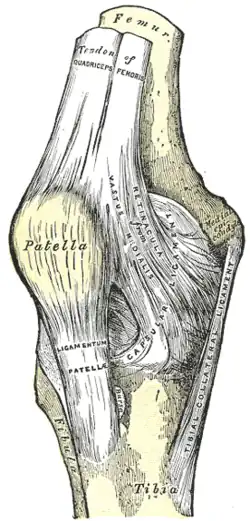

La rótula[1] (patella) es un hueso sesamoideo situado en el plano anterior de la articulación de la rodilla, engastada en el tendón del cuádriceps. Es aplanada, de forma triangular con vértice inferior, y su eje mayor mide unos 5 cm. El borde superior (base) y la cara anterior reciben las fibras del tendón del cuádriceps, y de su vértice parte el ligamento rotuliano que continúa al tendón del cuádriceps. La cara posterior (cara articular) posee la superficie articular para el fémur y, por debajo, una zona rugosa relacionada con formaciones adiposas de la articulación de la rodilla. La superficie articular consta de dos vertientes laterales separadas por una cresta roma central que se adaptan a la superficie rotuliana del fémur. Se considera el hueso sesamoideo más grande del cuerpo humano.

Se encuentra en la parte anterior de la rodilla. Su vértice se articula con el fémur. La rótula es un hueso plano y redondeado que se encuentra incluido en el tendón terminal del músculo cuadriceps femoral y está situado por delante de la extremidad inferior del fémur.

Las cuatro cabezas del cuádriceps (M. vasto intermedio, M. vasto lateral, M. vasto medial, M. recto femoral) se condensan en láminas tendinosas que confluyen en la proximidad de la rótula formando el tendón del cuádriceps, en cuyo espesor se localiza la rótula. El mayor componente de fibras emerge por el vértice inferior de la rótula y forma una potente cinta tendinosa denominada ligamento rotuliano que se inserta en la tuberosidad de la tibia.

Es convexa de arriba abajo y también en sentido transversal. Está cubierta de manojos fibrosos procedentes del tendón del cuádriceps, único músculo que se inserta en la misma. La separa de la piel una bolsa serosa llamada bolsa prerrotuliana y compleja. Su articulación es con la tibia y peroné.